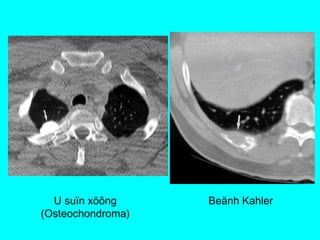

U XÖÔNG &PHAÀN MEÀM

Hình CT

-Huûy, bieán daïng xöông / Toån thöông phaàn meàm/

Xoùa lôùp môõ ngoøai maøng phoåi (+/-)

-Caàn khaûo saùt coù caûn quang.

Vai troø CT

-Ñaùnh giaù toát vò trí, möùc ñoä, lieân quan toån

thöông vôùi caùc caáu truùc khaùc ngöïc (phoåi, maøng

phoåi, trung thaát)

U suïn xöông

(Osteochondroma)

Beänh Kahler